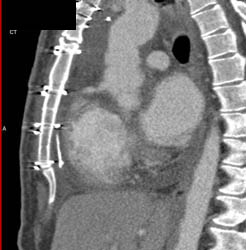

Coronary Artery Fistulae to Right Atrium- See Sequence of Images